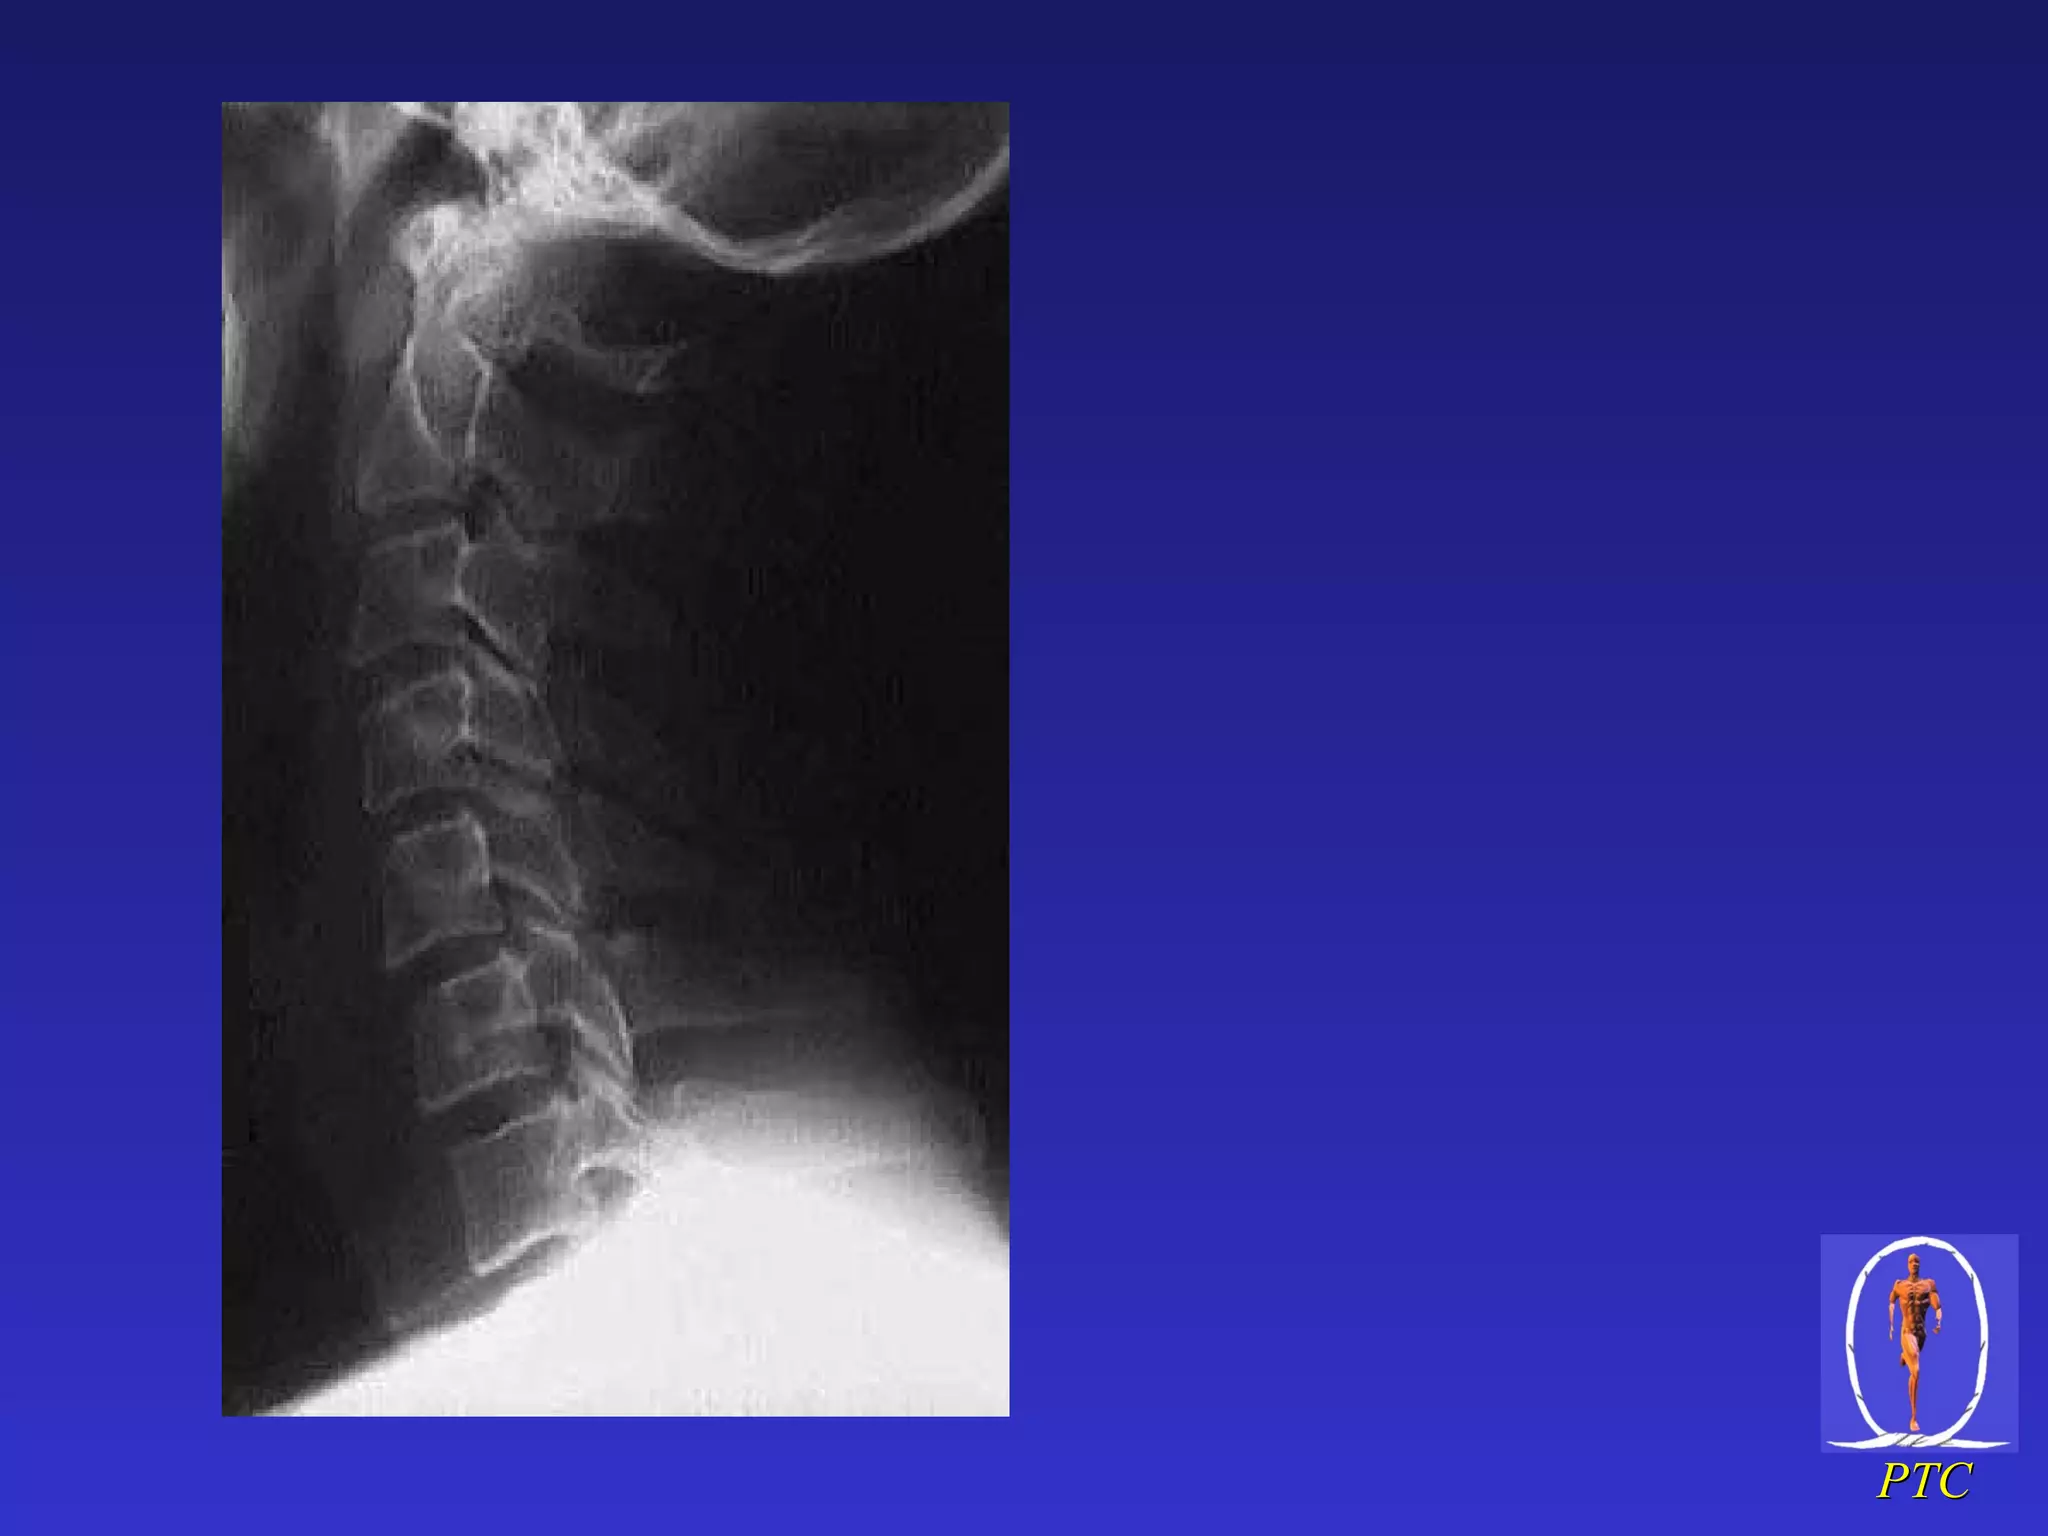

C/ spine  x-rays – lat view Identify Occipital condyles All seven cervical vertebrae Superior aspect of body of T1 Anatomic assessment Alignment – 5 lordotic curves Bones – contour Cartilage – discs and facet joints Soft tissues – pre-vertebral and inter-spinous space, ADI OC T1